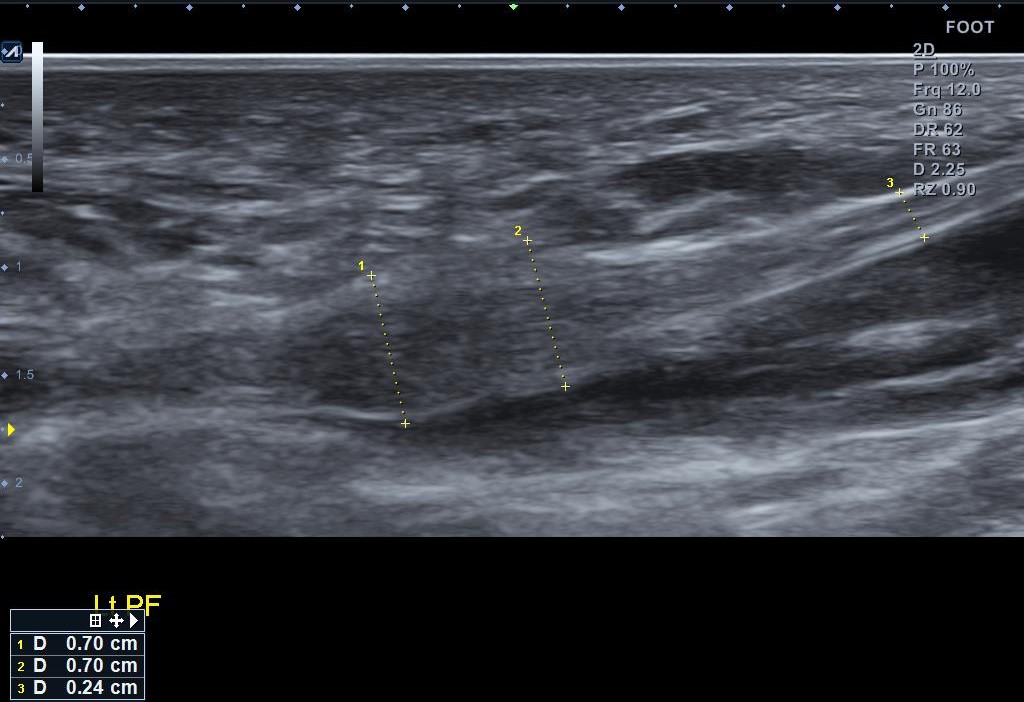

족저근막의 상태를 직접 확인하기 위해서는 초음파 검사가 꼭 필요한데요 초음파 검사를 통해 족저근막의 두께·염증 소견을 직접 확인합니다. 족저근막 두께 증가(보통 4mm 이상), 저에코(검게 보이는) 변화, 부착부(종골 내측 결절) 주변의 부종, 파열 여부, 필요 시 도플러로 활혈(염증성 혈류) 신호까지 확인할 수 있어, 현재 상태를 “눈으로” 보여주고 추적에도 유리합니다. 또한 종종 혼동되는 족저섬유종(결절성 변화) 등 감별에도 도움이 되는 검사가 초음파 검사입니다.